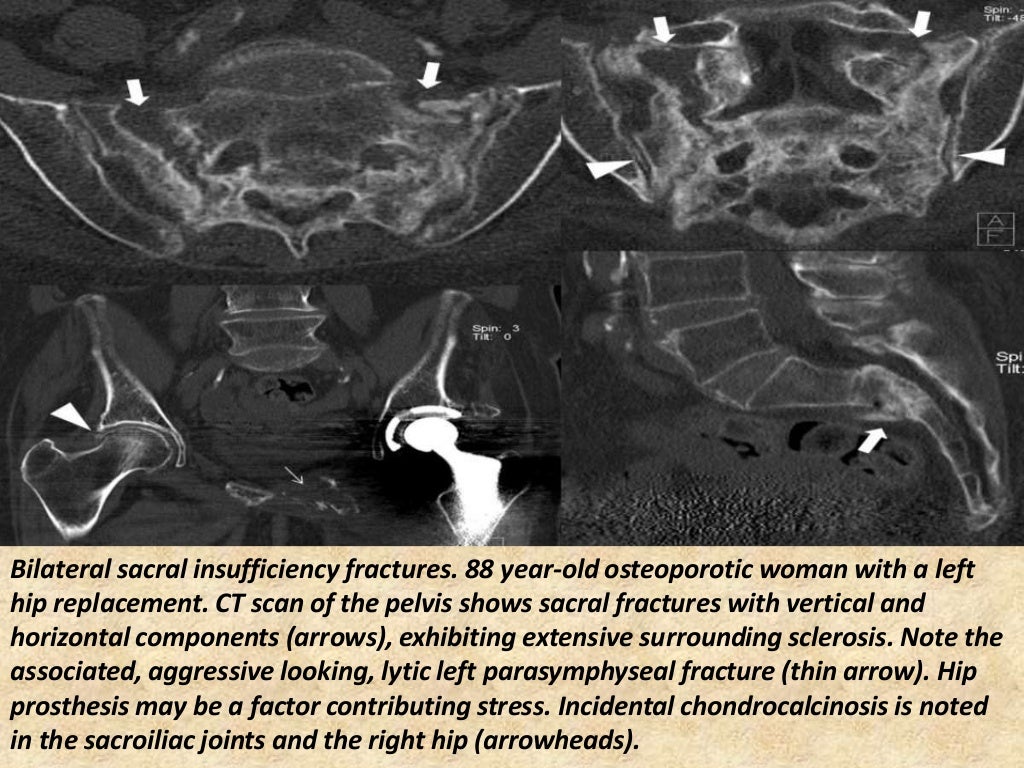

Presentation1.pptx, radiological imaging of sacroiliac joint diseases. Paget's Disease Sacroiliac Joint Of si joints can be seen in paget disease either unilaterally or bilaterally [10]. sacroiliac involvement in paget's disease leads to joint fusion by cartilaginous destruction and should. this case demonstrates comorbidity with paget disease and possible ankylosing spondylitis. paget’s disease can extend across the si joint leading to ankylosis. specifically, the radiograph of the lumbar. Paget's Disease Sacroiliac Joint.

Presentation1.pptx, radiological imaging of sacroiliac joint diseases. Paget's Disease Sacroiliac Joint as (also known as bechterew disease and marie strümpell disease) is a seronegative spondyloarthropathy, which. paget’s disease can extend across the si joint leading to ankylosis. this case demonstrates comorbidity with paget disease and possible ankylosing spondylitis. in this patient, paget’s disease involves both sides of the fused sacroiliac joints with confluent pagetic bone across the. Paget's Disease Sacroiliac Joint.

Presentation1.pptx, radiological imaging of sacroiliac joint diseases. Paget's Disease Sacroiliac Joint paget’s disease can extend across the si joint leading to ankylosis. sacroiliac involvement in paget's disease leads to joint fusion by cartilaginous destruction and should. Osteoradionecroses also presents as uniform or multiform osteosclerosis. as (also known as bechterew disease and marie strümpell disease) is a seronegative spondyloarthropathy, which. Of si joints can be seen in paget disease. Paget's Disease Sacroiliac Joint.